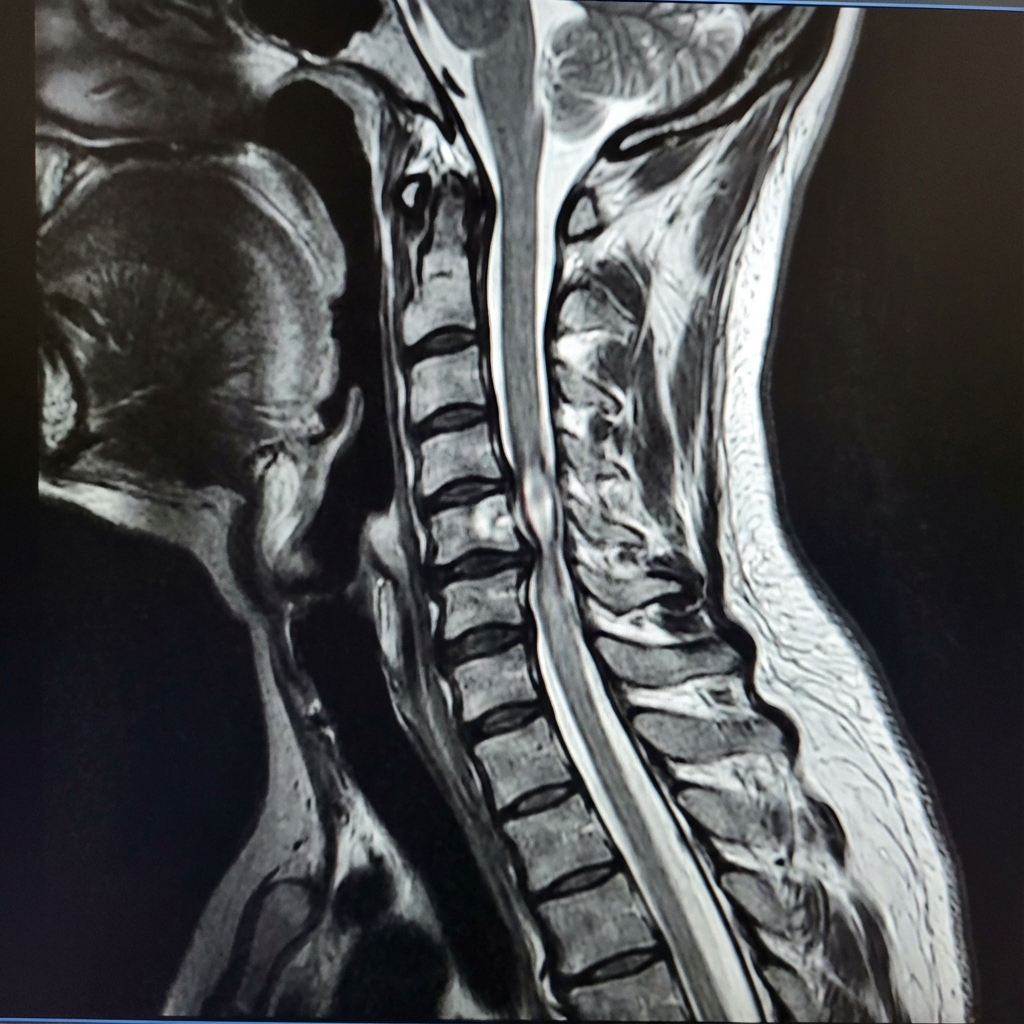

Sagittal T2-weighted MRI demonstrating multi-level cervical stenosis at C3-4, C4-5, and C5-6. There is cord compression with intramedullary T2 hyperintensity at C4-5 level indicating myelomalacia. The cord appears flattened and draped over disc-osteophyte complexes. Ligamentum flavum hypertrophy contributes posteriorly. This represents degenerative cervical myelopathy (DCM) requiring surgical decompression.